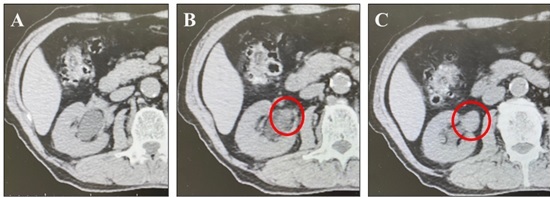

He also underwent radiation therapy for right renal pelvic cancer (Figure. 2A, B, C).

Figure 2. A, The dilated intrarenal pelvis. B, The ureteropelvic junction area is partially occupied with irregular mass (red circle). C: The extrarenal pelvis is filled with a substantial mass (red circle). However, invasion into the surrounding area is not evident. It is judged to be cT3.